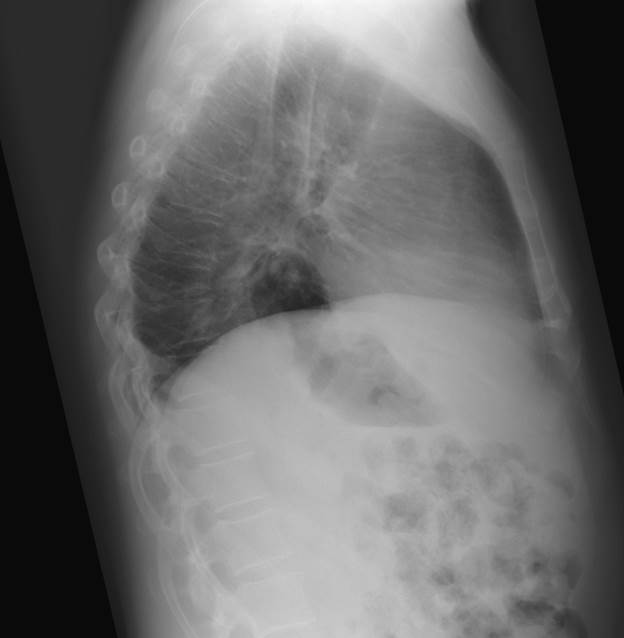

Upright chest Xray showing large intrathoracic hiatal hernia between Will A Chest X Ray Show Hiatal Hernia They will look at your past health. How is a hiatal hernia diagnosed? You may also have tests,. At other times, a hiatal hernia may be suspected in. Tests that can diagnose a hiatal hernia include: A hiatal hernia is often discovered during a test or procedure to determine the cause of heartburn or pain in the chest or upper. Will A Chest X Ray Show Hiatal Hernia.

Will A Chest X Ray Show Hiatal Hernia . It will classically appear as a mass with an air fluid level behind the heart. A hiatal hernia is often discovered during a test or procedure to determine the cause of heartburn or pain in the chest or upper abdomen. Tests that can diagnose a hiatal hernia include: How is a hiatal hernia diagnosed? You may also have tests,. At other times, a hiatal hernia may be suspected in. Your healthcare provider will give you a physical exam. Most hiatal hernias are found incidentally, and they are usually discovered on routine chest radiographs or computed tomography (ct) scans performed for unrelated symptoms. They will look at your past health.

It will classically appear as a mass with an air fluid level behind the heart. You may also have tests,. A hiatal hernia is often discovered during a test or procedure to determine the cause of heartburn or pain in the chest or upper abdomen. They will look at your past health. Most hiatal hernias are found incidentally, and they are usually discovered on routine chest radiographs or computed tomography (ct) scans performed for unrelated symptoms. Tests that can diagnose a hiatal hernia include: How is a hiatal hernia diagnosed? Your healthcare provider will give you a physical exam. At other times, a hiatal hernia may be suspected in.